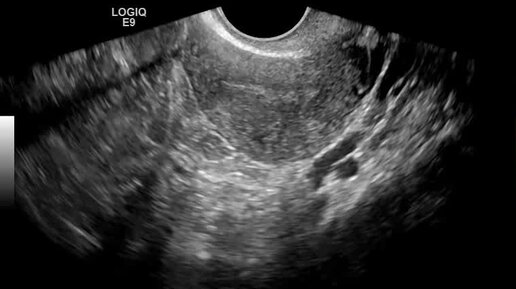

Видео: яичник расположен по задней поверхности матки

Ультразвуковые находки от врача УЗД Зорина Я.П.